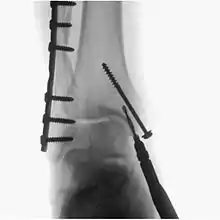

Fluoroscopy has become an important tool in medical imaging to render moving pictures during a surgery or any other procedure.

A fluoroscopy X-ray machine is a great asset during surgery for implants

Surgical fluoroscopy

Fluoroscopy is used in various types of surgical procedure, such as orthopaedic surgery and podiatric surgery. In both of those, it is used to guide fracture reduction and in use in certain procedures that have extensive hardware.[5]